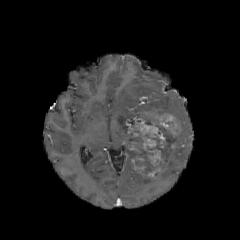

(a) (b) (c) (d) (e)

Comparison to Competing Methods:

We have compared the performance of our model against the most popular deep learning-based semantic segmentation networks, U-Net [9] and V-Net [7] (Fig. 3). Our model outperforms both by a considerable margin in all evaluation metrics. In particular, U-Net performs poorly in most cases due to the high false positive of its segmentation predictions, as well as the imprecision of its boundaries. The powerful residual block in the V-Net architecture seems to alleviate these issues to some extent, but V-Net also fails to produce high-quality boundary predictions. The emphasis of learning useful edge-related information during the training of our network appears to effectively regularize the network such that boundary accuracy is improved.